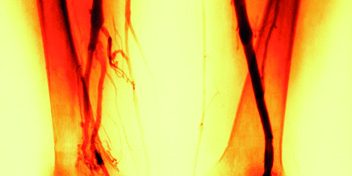

Selon l’InVS (*), la maladie thromboembolique veineuse est l’une des principales pathologies de la grossesse et du postpartum et la 2e cause de mortalité maternelle. La thrombose veineuse profonde ou phlébite touche environ 1,8 femmes enceintes sur 1 000 et le nombre de cas augmente depuis 5 ans.

Pour prévenir cette maladie, les recommandations françaises et internationales préconisent le port de compression médicale du début de grossesse jusqu’à plusieurs semaines après l’accouchement, qu’il soit par voie basse ou césarienne.